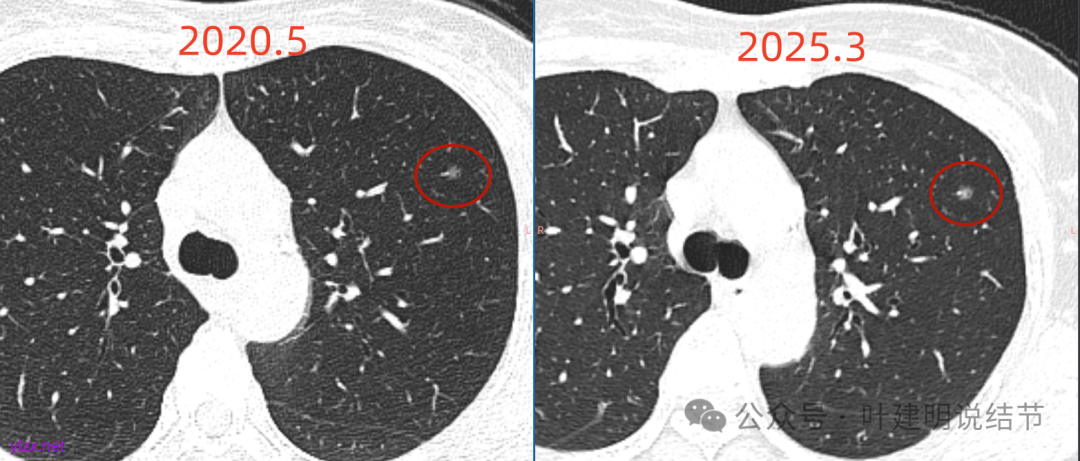

再看2020年5月时的主病灶以及两次对比的影像:

上图示对比,密度略有增加,但并不十分厉害。

两肺多发磨玻璃结节,我们主要看最主要的病灶有没有风险或者有没有进展就可以。我是先看2025年的,黄色的微小磨玻璃结节,密度很低,但是轮廓较为清楚,需要考虑肺泡上皮增生或者肺泡间隔增宽,严格意义上应该没有算肺癌,但是以后有可能会发展到不典型增生或者原位癌,当然也可能永远发展不到那个程度,所以目前不需要管;蓝色的到底是肺泡上皮增生还是少许慢性炎不太好确定,因为轮廓稍显模糊,但它又是磨玻璃密度,总归近期是能够随访的;橘色的密度比黄色的略高,有可能会使肺泡上皮增生或者不典型增生,目前也仍可以随访;粉色的是主病灶,位于左肺上叶,混合密度,表面毛糙,由小血管进入,单次看需要考虑微浸润性腺癌可能性较大。然后我们再来看2020年的影像,因为除了粉色的其他的都没有风险,所以不需要一一去找出来,重点关注粉色这处当时是怎样的。我们发现这个病灶5年前就有,也有小血管进入,也有表面毛糙,也是磨玻璃密度,但是当时磨玻璃当中没有实性的成分,是纯磨玻璃伴微小血管进入。对比起来看,这个病灶在5年当中略有进展,原来应该是腺体前驱病变,现在应该是原位癌或者微浸润性腺癌。那么是不是现在就到了一定得马上手术的程度呢?这个仍然可能是不同医生意见会有出入的。假如说从再随访是不是马上会转移来讲,这么小的肿瘤,发展这么慢,而且仍然含有磨玻璃成分,病理考虑与微浸润性腺癌可能性较大,应该仍然不至于说没有随访的空间。但是如果继续随反思想压力比较大,以及即便在随访后续仍然总得要开刀来说,加上病灶位置靠胸膜并不远,简单的单孔胸腔镜楔形切除就能解决问题,将有一定风险的这个病灶切了,同样是可行的。这需要你自己权衡决定。我没有办法100%给十分确切的意见。但是如果从倾向性来讲,由于是多发病灶,加上年纪还轻,风险还不是很大,稍微清一下雨6~9个月复查,有进展病风险再增加再考虑手术。意见供你参考!